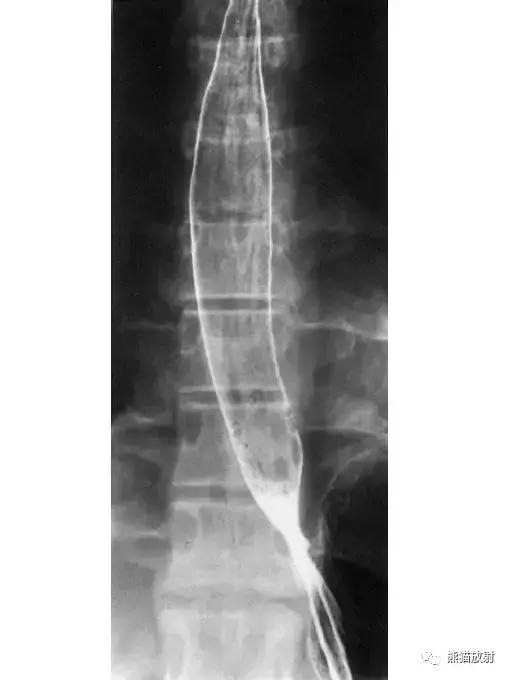

四、食管和胃

图7 食管和胃造影

图8 食管和胃解剖示意图。1 食管远段,2 胃食管角,3 食管腹段,4 食管裂孔,5 贲门